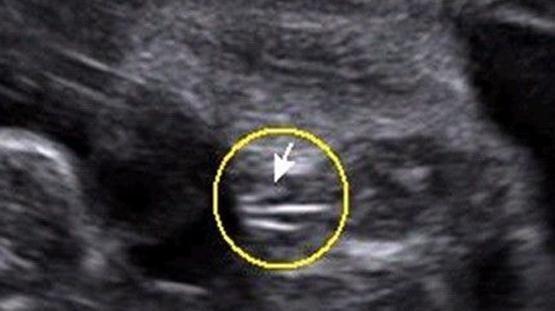

女宝宝的b超图

女宝宝B超

三条白线是明显的女宝特征,如果没有看到明显的三条白线,就看两腿之间有没有突出的东东,且中间有小凹槽的,就是女宝。